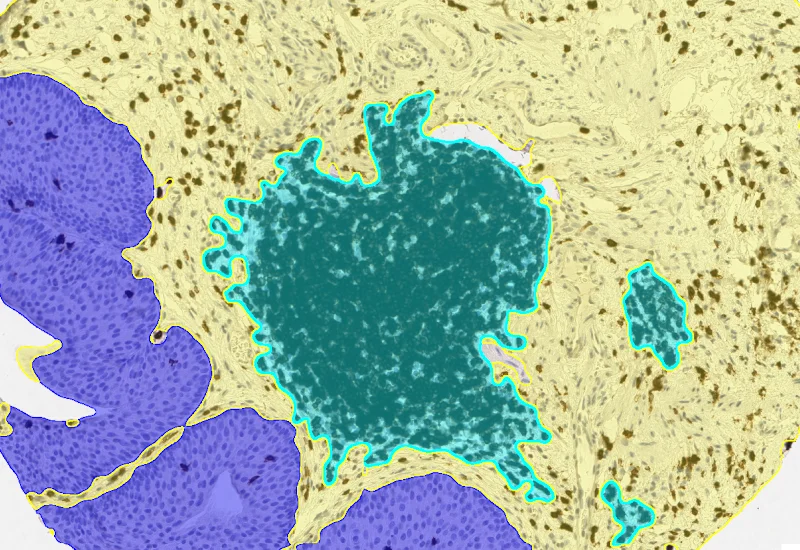

Tumor/Stroma/lymphoid cluster detection

Proximity map tumor

Proximity map lymphoid cluster

- AI classifier: Segment ROI/sample into Tumor, Stroma, and Lymphocyte Clusters; retrain classifier using manual annotations if required.